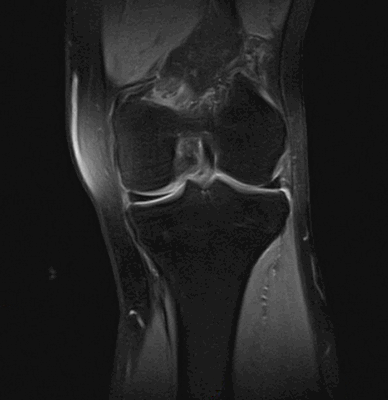

На МРТ хорошо прослеживаются все стадии этого процесса. На томограмме определяется выпот синовиальной жидкости и подхрящевая костная киста при остеоартрозе коленного сустава.

Фронтальный срез МРТ коленного сустава